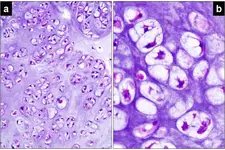

Kıkırdak Doku Çeşitleri Kıkırdak doku, bağ dokuları arasında yer alan, esnek ve dayanıklı bir yapıya sahip olan dokulardır. Farklı türleri ve işlevleri, vücudun çeşitli bölgelerinde önemli roller üstlenmektedir. Bu makalede, kıkırdak dokunun çeşitleri ve özellikleri detaylı bir şekilde ele alınacaktır. Kıkırdak Doku Türleri Kıkırdak doku üç ana türde sınıflandırılmaktadır: hyalin kıkırdak, elastik kıkırdak ve fibröz kıkırdak. Her bir tür, farklı yapısal özelliklere ve işlevsel amaçlara sahiptir.